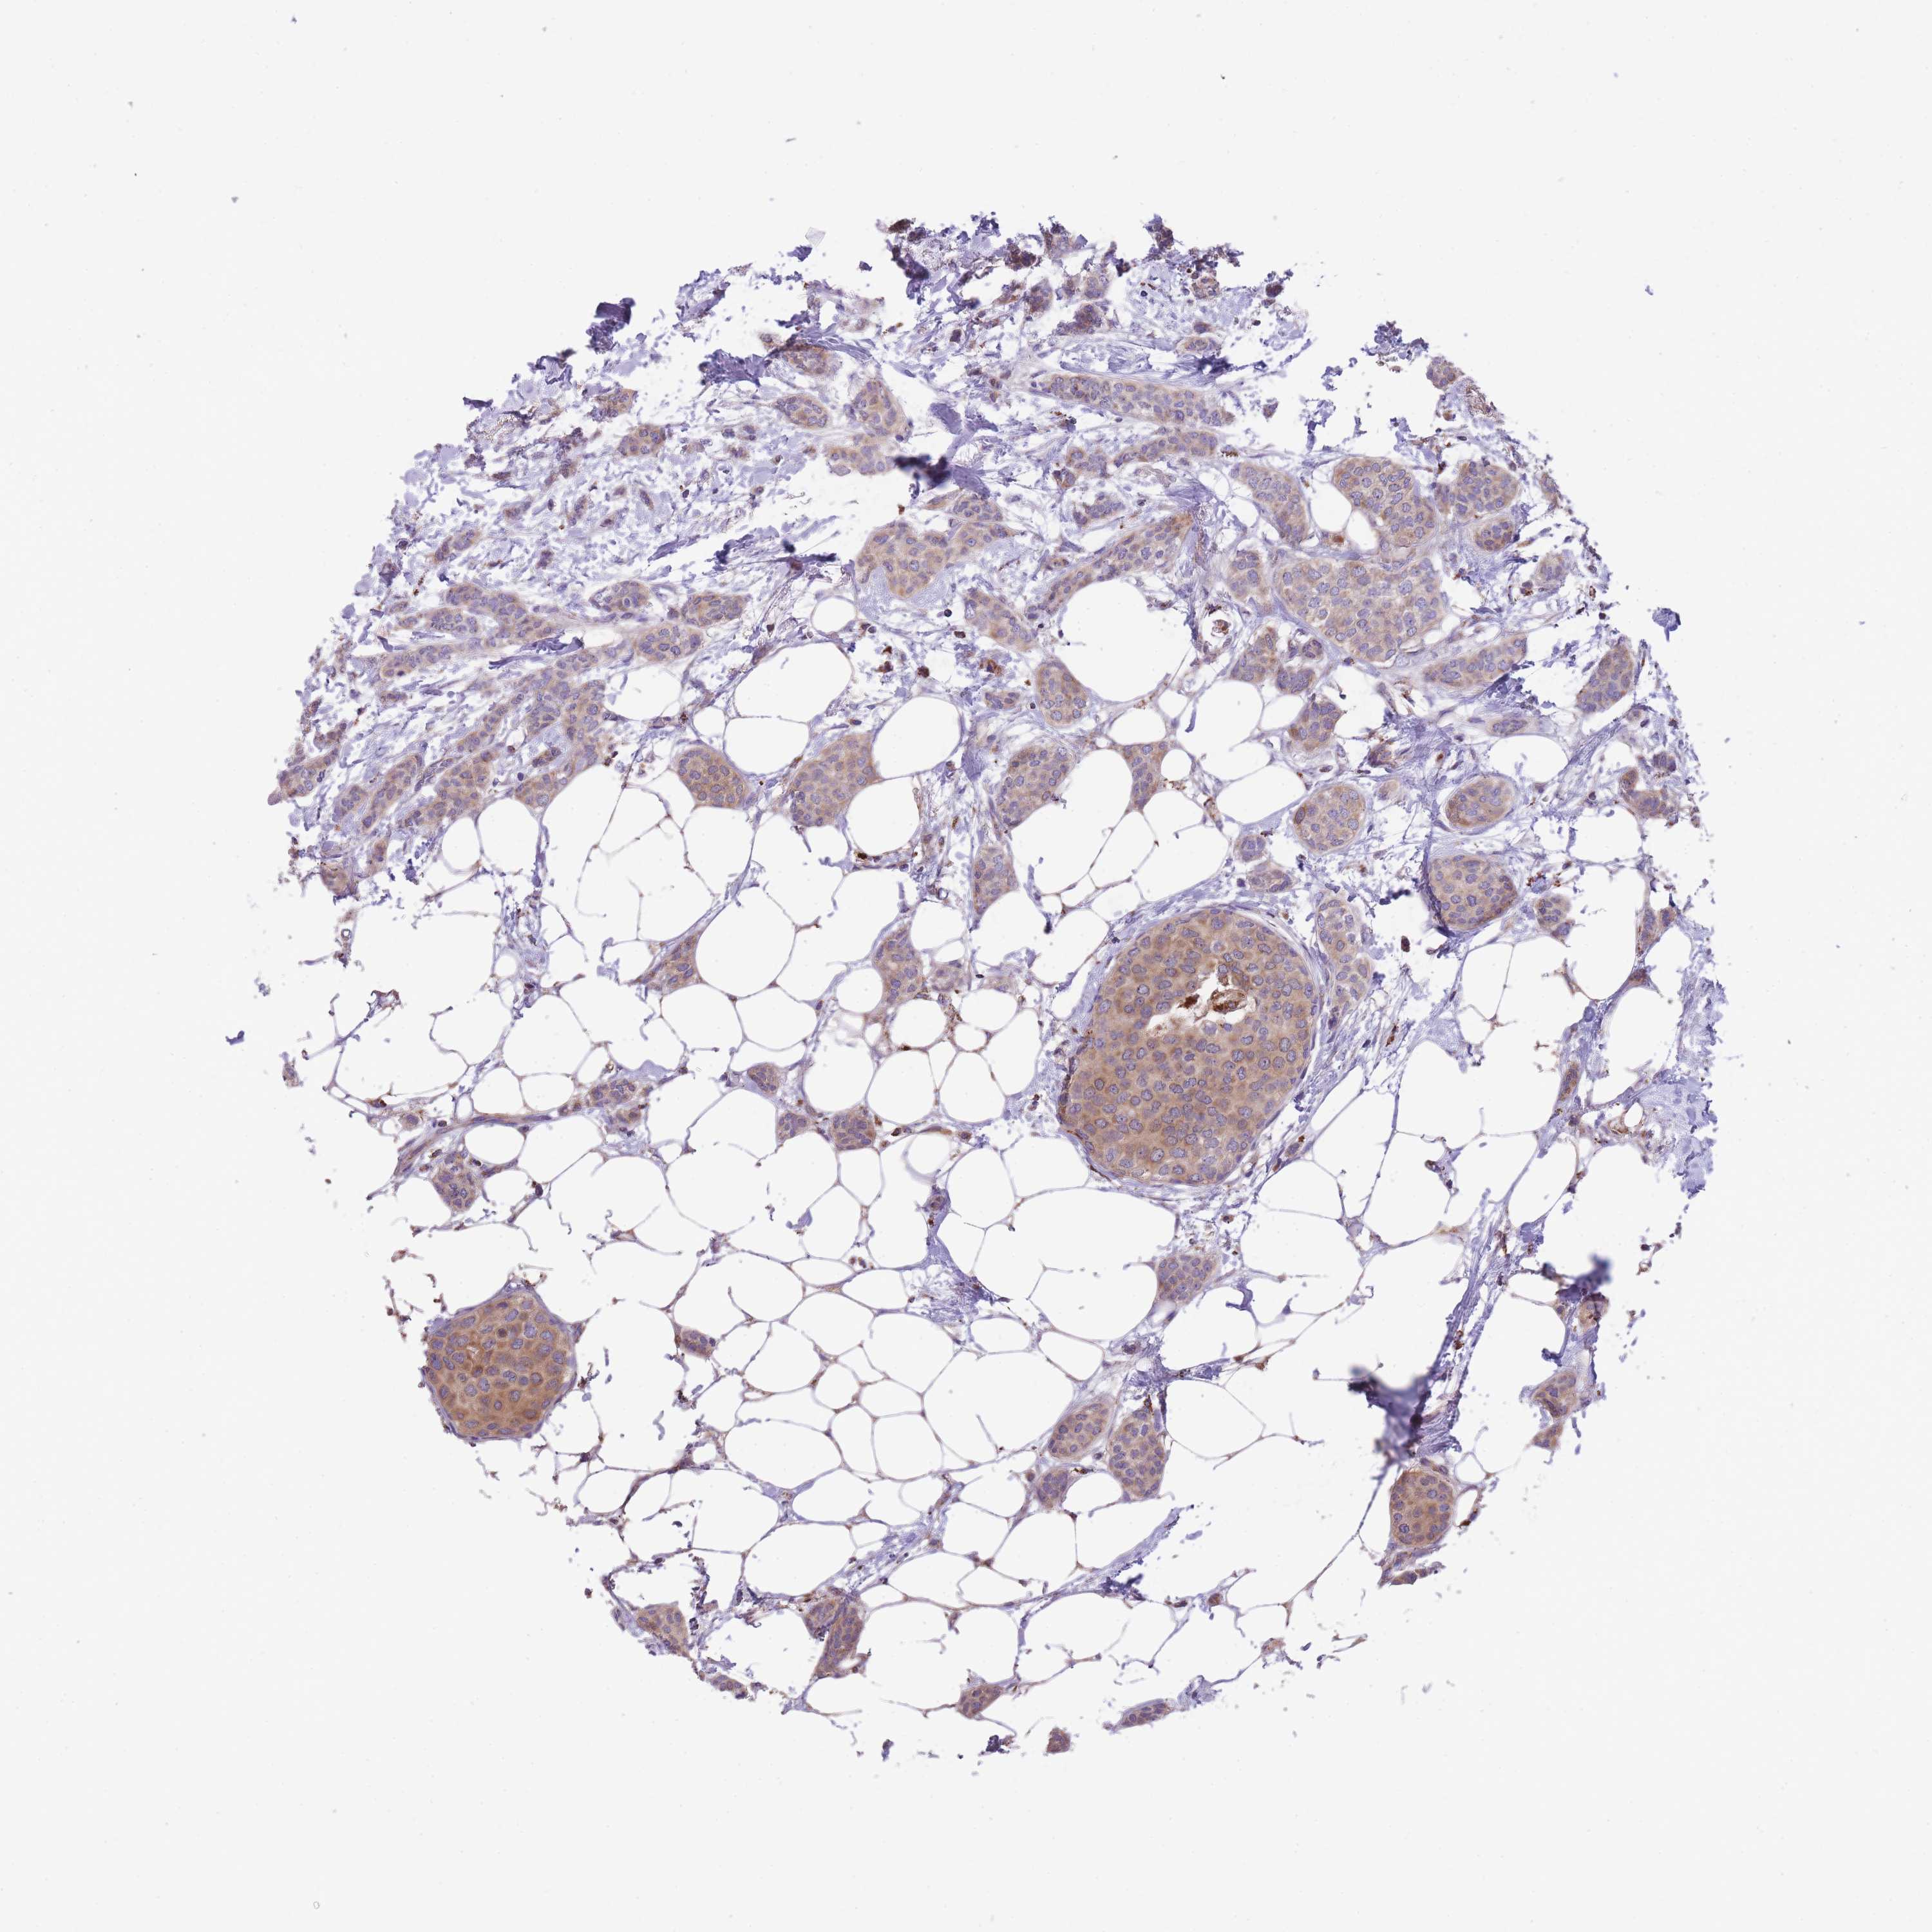

CANCER BREAST CANCER Show tissue menu

BRCA TCGA BRCA VALIDATION PROTEIN EXPRESSION